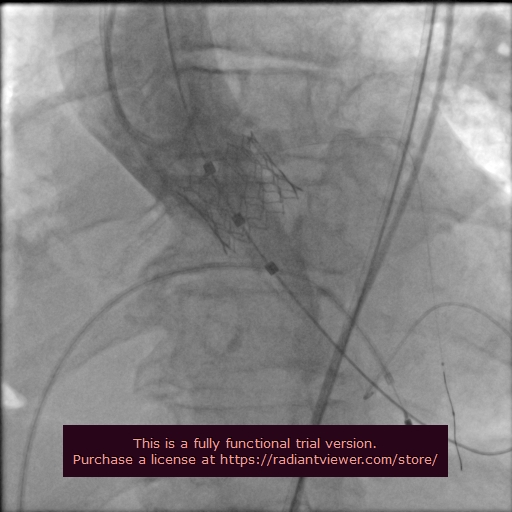

Geçtiğimiz günlerde Prof. Dr. İlker Gül başkanlığında Kardiyoloji, Kalp Damar Cerrahisi ve Anesteziyoloji ve Reanimasyon Anabilim Dalı ile anjiyografi laboratuvarı ekipleri tarafından gerçekleştirilen işlemle Ali Güvensoy kalp sağlığına tekrar kavuştu.

İşlem öncesi yoğun bakımda solunum makinesi desteğinde olan hastanın akciğer ödemi ve kalp yetersizliği nedeniyle hayati riski bulunduğunu kaydeden Prof. Dr. İlker Gül, TAVİ işleminden bir gün sonra Güvensoy’un genel durumunun hızla toparladığını, yataklı servise alındığını, birkaç gün sonra ise sağlıklı bir şekilde taburcu edildiğini söyledi.